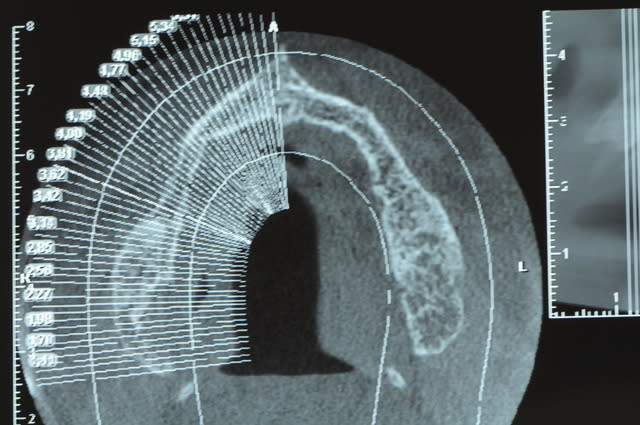

Une petite étude de ton cas D57

Les zones exploitables radiologiquement parlant:

Coupes implant

2,3 40100

4,96 35130 avec sinus lift mais difficile

5,25 35150

6,02 35130

6,78 35115 après réduction de hauteur de crête

7,26 35115 après réduction de hauteur de crête

8,51 35150

10,43 40115 ou 50115

11,10 40115

Ce qui nous fait 9 implants possible évidement avec un comblement de sinus on augmenterait encore les zones implantable mais ce n’est pas le but recherché, avec 8 (4+4) il doit être possible de faire une belle barre support de complet